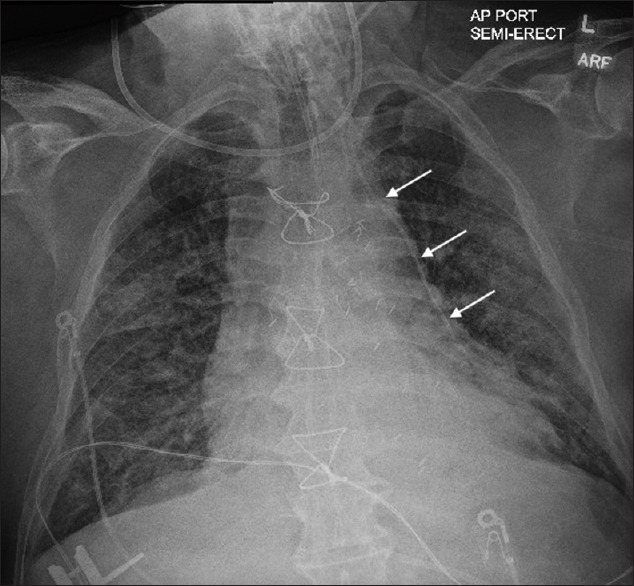

Misplacement of a Left Internal Jugular Central Venous Catheter in the Pericardiophrenic Vein.